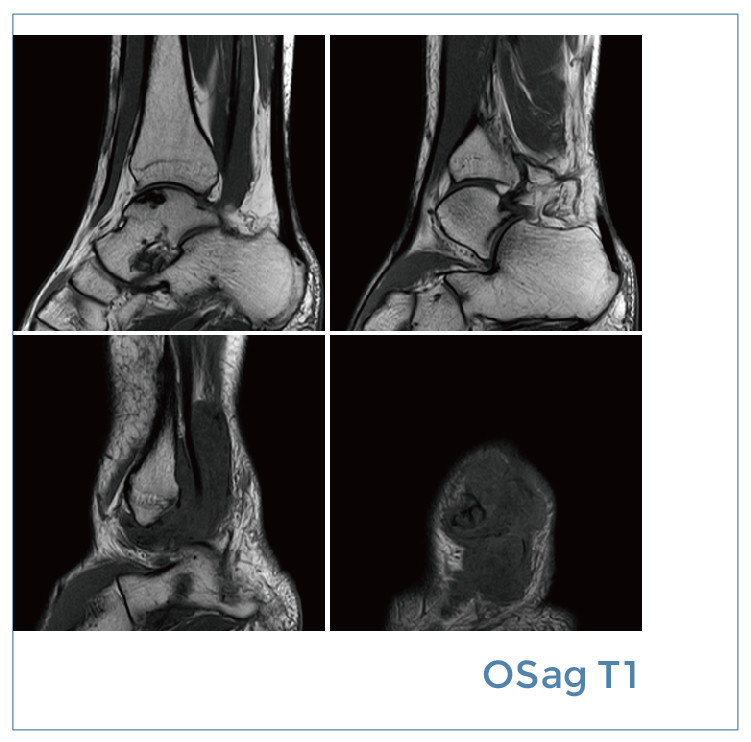

【朗润影像档案】磁共振影像病例分享(编号20191213)